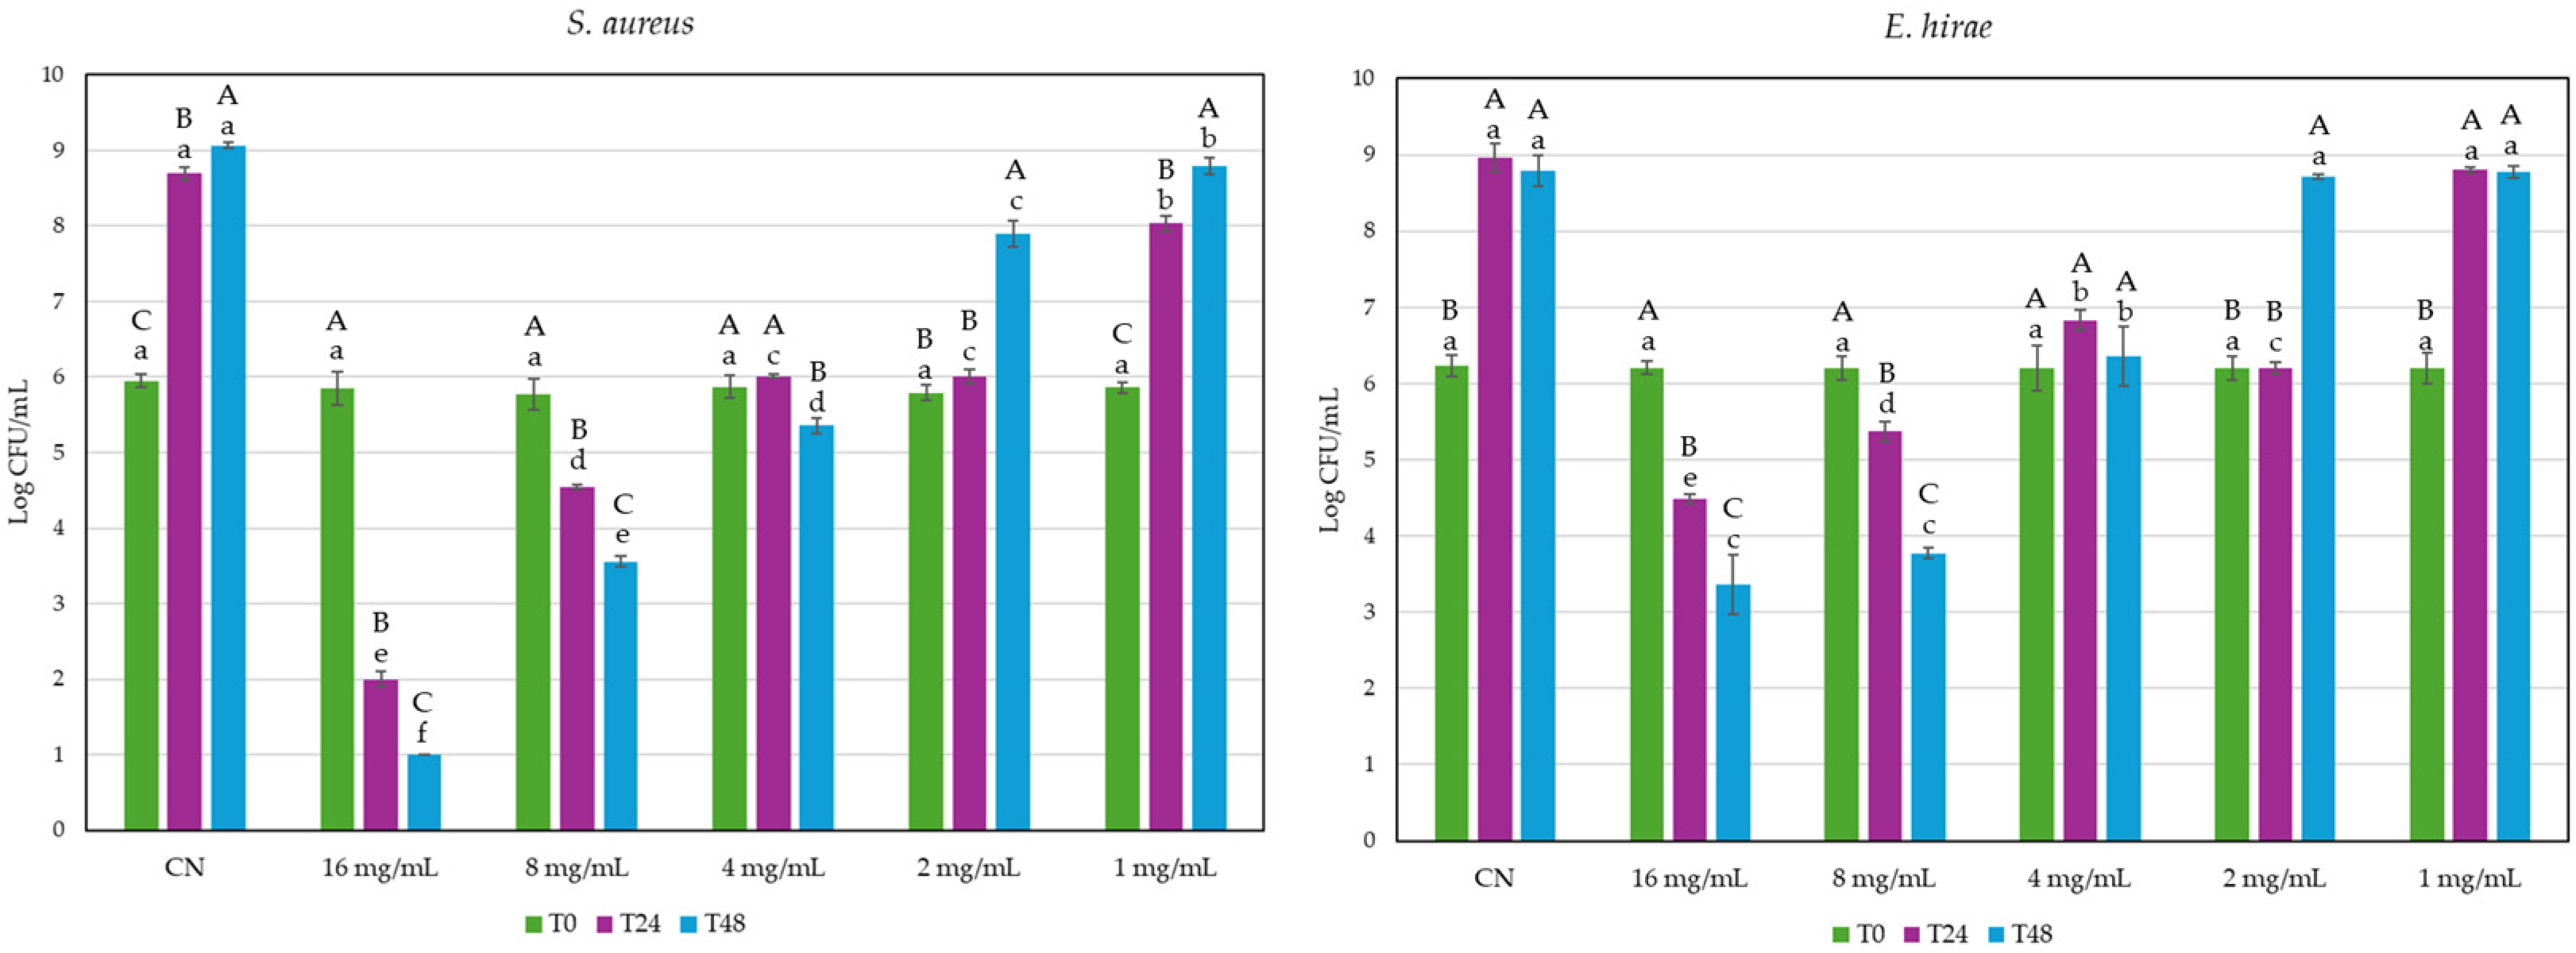

2.2. Antibacterial Activity of GG Root Extract

3.5. Antibacterial Activity of GG Root Extract